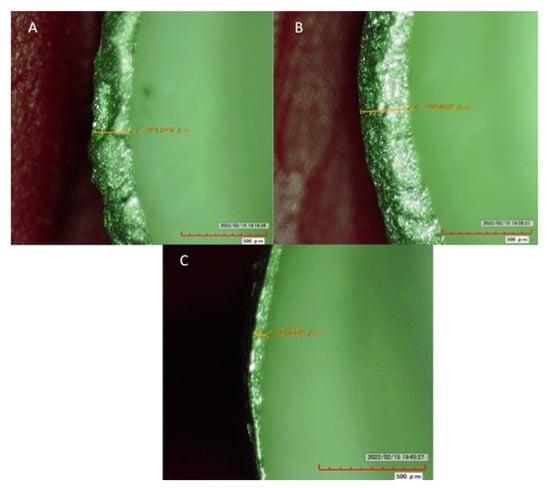

2.8. Assessment of Marginal Misfit